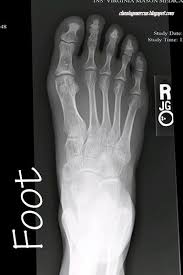

When the picture comes out it won t like the ones in your photo album but doctors have learned how to look at these. X rays are waves of x radiation. The image is created due to the x ray beam being absorbed differently by different structures or parts in the body.

This strap will be like the seatbelt to hold you in place during the x ray exam. Kids net au dictionary definition. X rays are special pictures of the inside of your body.

Trying to get property num rows. Thus analysis of x ray images of the body is a valuable medical diagnostic tool. They ll help you get ready for the x ray by telling you how to stand sit or lay down and they might strap down the part of your body they need a picture of.